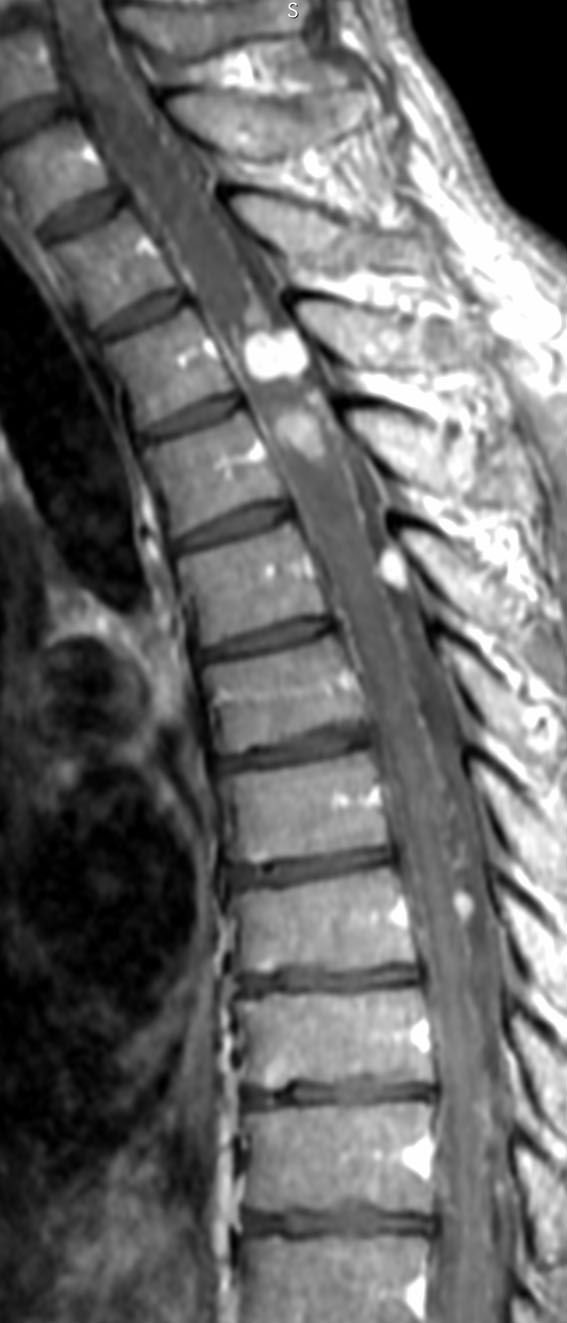

摘出後5年,左下肢違和感で発症しました。脊髄表面に無数のmassがあり,脊髄軟膜も線状に増強されます。髄液播種の所見です。さらに2年後(右の画像)では頭蓋内の脳槽にも多数の転移を生じました。頸髄髄内は表面のものが浸潤したものです。この例は,フォンヒッペルリンドウ病の多発血管芽腫ではなく,髄液播種転移を示しています。